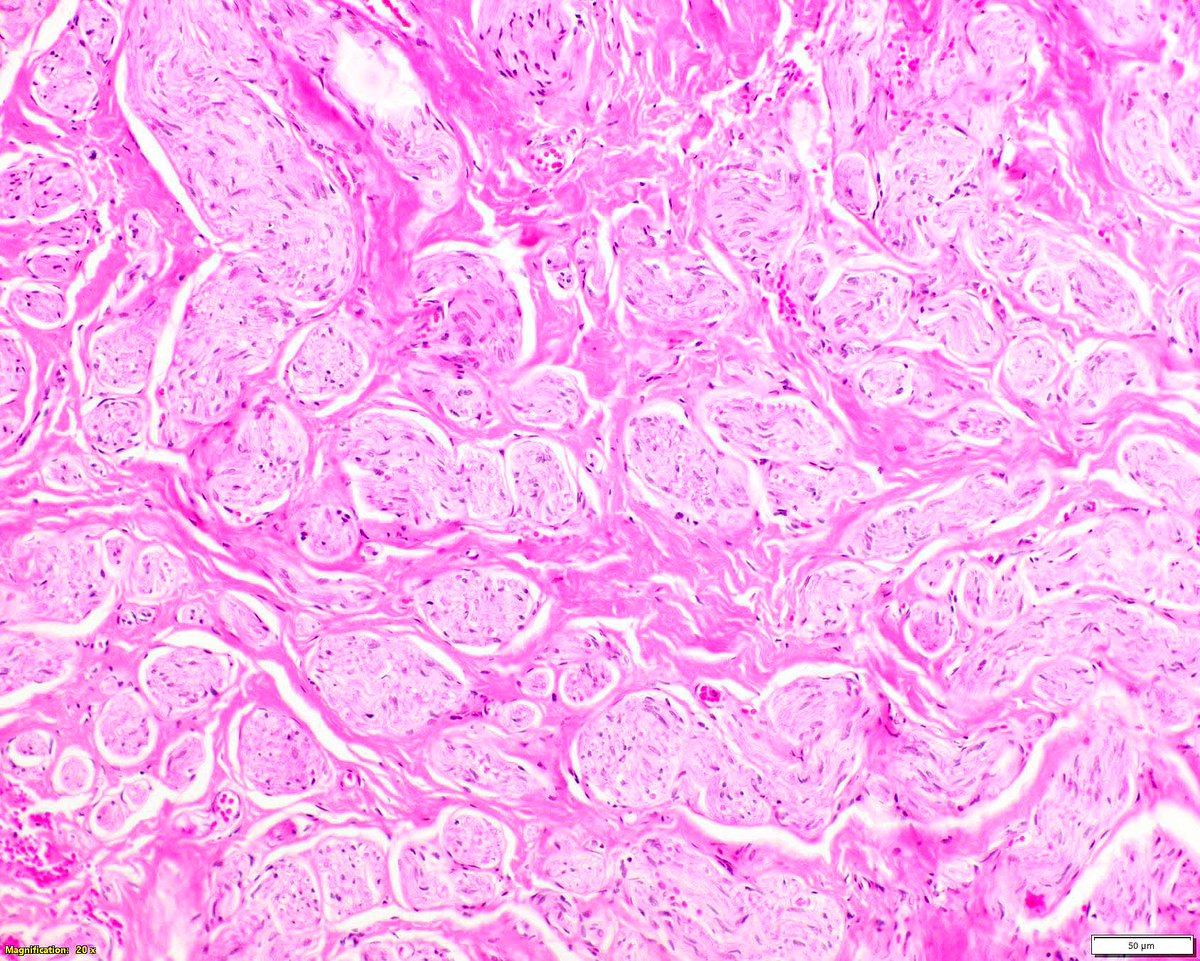

In traumatic neuromas, the individual nerve packets are each cuffed by perineurium. A vintage Mod Pathol study demonstrated this. Hirose T, Tani T, Shimada T, Ishizawa K, Shimada S, Sano T. Immunohistochemical demonstration of EMA/Glut1-positive perineurial cells and

In traumatic neuromas, the individual nerve packets are each cuffed by perineurium. A vintage Mod Pathol study demonstrated this.

Hirose T, Tani T, Shimada T, Ishizawa K, Shimada S, Sano T. Immunohistochemical demonstration of EMA/Glut1-positive perineurial cells and